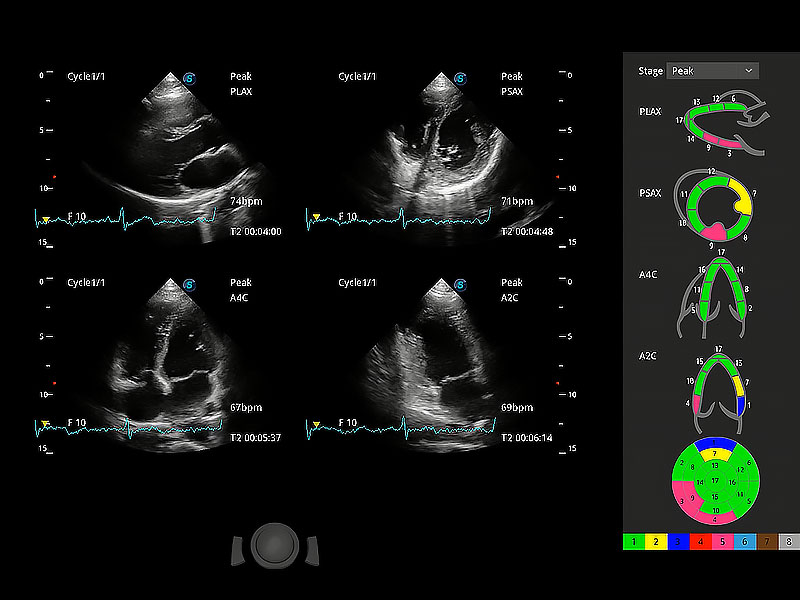

ProPet 80 配備了豐富的心臟探頭群、先進(jìn)的成像技術(shù)和專業(yè)的心臟測(cè)量工具,可幫助動(dòng)物醫(yī)生為不同體型和生理結(jié)構(gòu)的動(dòng)物提供心臟和心肌功能的全面評(píng)估。

通過(guò)心肌識(shí)別技術(shù)與二維斑點(diǎn)追蹤技術(shù)相結(jié)合,對(duì)心臟的超聲圖像進(jìn)行量化分析。計(jì)算心肌17個(gè)節(jié)段的應(yīng)變、應(yīng)變率、速度、位移等,并通過(guò)牛眼圖的形式進(jìn)行呈現(xiàn)。

具備多種協(xié)議可選,同時(shí)支持17階段劃分法和專業(yè)的SE報(bào)告。